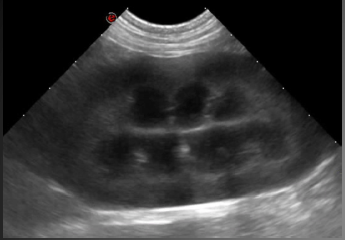

• Expliquer les principes de formation de l’image échographique et identifier les paramètres techniques nécessaires à l’obtention d’une image de qualité : choix et réglages de l’appareil, préparation de l’animal, protocole de réalisation de l’examen, etc.

– Identifier son aspect échographique normal

Pour chaque organe, un rappel illustré est proposé, couvrant l’anatomie topographique, la technique d’exploration échographique, et l’aspect échographique normal.

Le formateur réalise une démonstration en direct sur animal, illustrant la méthodologie d’exploration et l’identification de l’aspect normal de l’organe.

• Les rappels anatomiques et la présentation des images normales sont présentés par projection multimédia